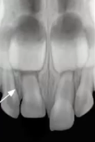

Has the follice been invaded?

No

Yes (elongation = palatal dispacement)